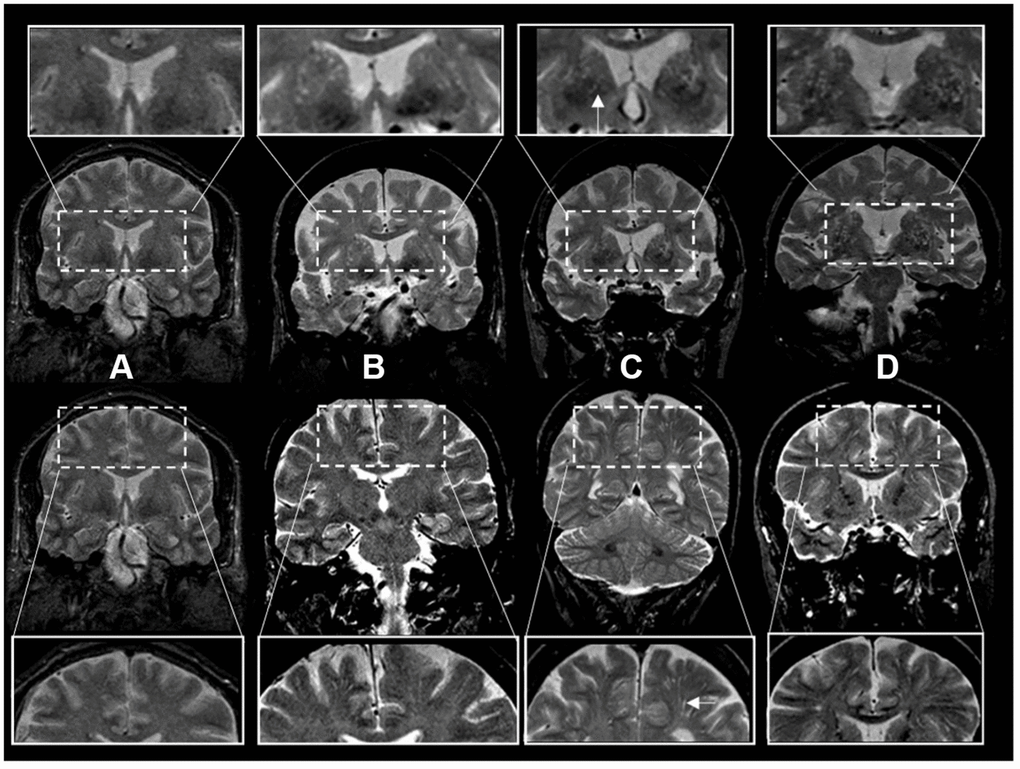

Figure 2. Enlarged perivascular space burden using ratings in coronal T2-weighted MRI sequences. *Top rows: basal ganglia region. Bottom rows: centrum semiovale region. The inserts represent a closer view. White arrows point to individual examples of enlarged perivascular spaces (panel C inserts). †Grades of ePVS burden are based on T2 weighted coronal views. (A) Grade I (0-10), (B) Grade II (10-20) (C) Grade III (20-40) (D) Grade IV (40+).

Scans were rated by three investigators (JRR, PP, AS) blinded to the subjects’ demographic and clinical information. T2-weighted axial MRI sequences were the main sequence used for rating ePVS following a validated method [11]. Brain topography of ePVS was classified as centrum semiovale (CSO) and basal ganglia (BG). We also analyzed a mixed group including ePVS in both regions. The burden of ePVS in each region was categorized into grades based on ePVS counts: grade I (1-10), II (11-20), III (20-40) and IV (>40). In a subset of legacy scans from an older dataset, coronal acquisitions were of higher resolution than axial views and were used for ratings (N=1122). For these ratings using coronal views to approximate ratings using axial views we assessed the entire BG region in all slices above the anterior commissure and below the level of the roof of the lateral ventricles. Ratings were based on ePVS burden in the BG bilaterally or in case of presence of large incidental lesions (such as large covert infarcts – without corresponding clinical stroke or TIA event) in the contralesional side. Ratings of the CSO region were performed evaluating the corona radiata, above the level of the lateral ventricles, and subcortical white matter. We categorized burden of ePVS using the same categories as in axial views (Figure 2). In a subset of scans with available high-resolution axial and coronal reconstructions, we compared ePVS ratings in BG and CSO regions based on axial versus coronal sequences. ePVS ratings in BG and CSO were done on 20 scans rated in random order in two separate occasions using axial sequences first, and repeating ratings with the coronal sequence after changing scan order randomly and blinded to the axial ratings. Ratings in axial and coronal sequences were highly correlated with an intraclass correlation (ICC)=0.91.